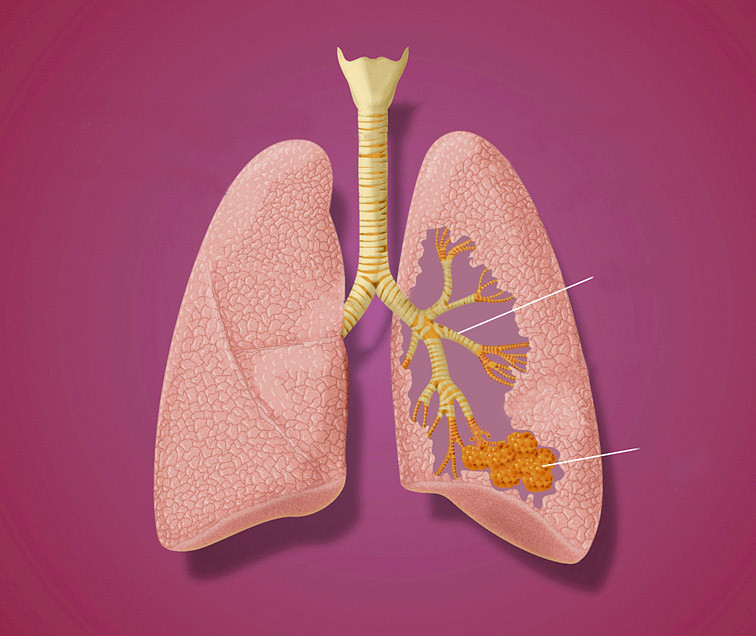

Бронхит

Ветвящиеся бронхи похожи на два раскидистых дерева. Они покрыты слизистой оболочкой – ее воспаление и называется бронхитом.

Пневмония

Возбудители пневмонии (бактерии, вирусы или грибки) передаются воздушно-капельным путем. Поэтому заболеть может каждый. Но в группе особого риска – дети до пяти лет, пожилые и люди с хроническими болезнями. Пневмония очень опасна. Поэтому не медли, если тебя беспокоят сильный кашель с мокротой, повышенная потливость, жар или озноб, ты ощущаешь нехватку воздуха или боль в груди. Основное лечение пневмонии – антибиотики. Но гораздо проще ее предупредить. Лучший способ – укреплять иммунитет. Для людей из группы риска рекомендуется дополнительная защита – вакцинация. Прививка защищает от пневмококковой инфекции, которая чаще всего вызывает пневмонию. Но перед тем, как ее сделать, проконсультируйся с врачом.

Как мы дышим?

Когда мы делаем вдох, воздух попадает в гортань, затем в трахею и бронхи. Проходя этот путь, воздух согревается, очищается от пыли, бактерий и вирусов и попадает в легкие.

Легкие состоят из крохотных пузырьков (альвеол). При вдохе легкие расширяются, альвеолы наполняются воздухом.

Струящаяся по сосудам кровь вбирает в себя кислород и разносит его по клеткам. А кровь отдает альвеолам углекислый газ – его мы и выдыхаем.